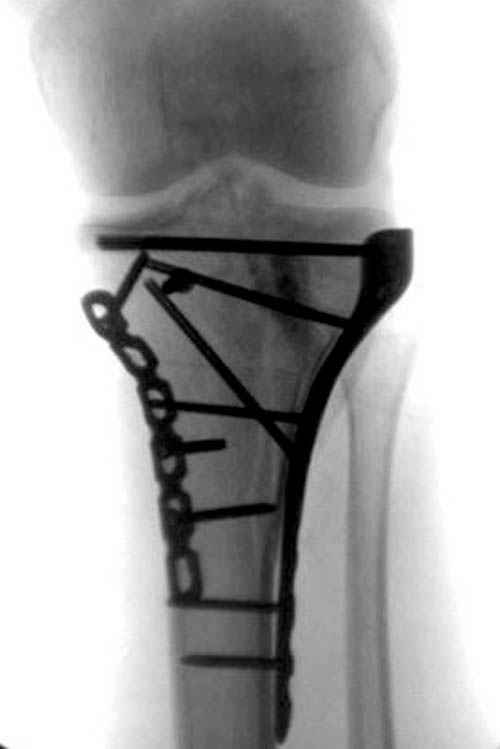

Трудно поверить, что разрекламированная Ортопедическая школа Восточной Украины позволяет такие странные снимки? На прямом снимке сохранен общий контур плато, но не известна судьба импрессии суставной поверхности. На полубоковой?, оставлен без репозиции задне-медиальный отдел, и навряд ли после такой фиксации можно удовлетвориться результатом.

Такая ситуация характерна для многих, когда принимается ошибочное решение, т.е пытаются фиксировать одним имплантом переломы двух мыщелков. Латеральная пластина приемлема только для тех случаев, когда сохраняется интактным медиальный диафизарный кортекс и отсутствует фрагментация на верхушке медиального перелома.

Представленные снимки не информативны, нужны отдельные качественные снимки коленного сустава и голени без ротации.

Надеюсь, представленные снимки разных случаев помогут разобраться в тактике, и критика примется без личной обиды.